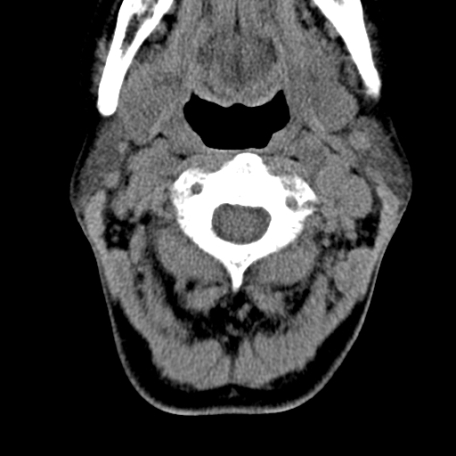

标题: CT24010:患者女56岁双侧甲状腺摘除术后一月复查,患者现感 [打印本页]

标题: CT24010:患者女56岁双侧甲状腺摘除术后一月复查,患者现感

甲状腺术后复发,现在甲状腺区域仍有密度不均匀之软组织密度影。

甲状腺区域密度不均匀密度影,应该是术后改变,要鉴别是否复发,建议增强检查。

“甲状腺摘除术后一月复查”,有病理吗?考虑术后复发,可能是恶性,颌下及左侧颈部淋巴结有肿大。

考虑术后复发,并颈部淋巴结肿大。请结合临床。

双侧甲状腺肿大,周围结构不清,术后复发时间有点短,考虑出血并感染。